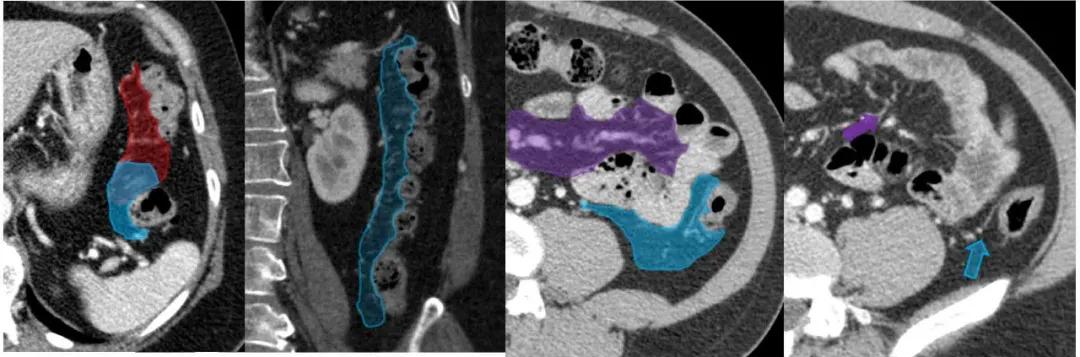

回盲部:小肠系膜(紫色)和右侧结肠系膜(黄色)与回结肠血管(蓝箭头)的汇合处。

右侧结肠系膜(黄色)和横结肠系膜(红色)间的汇合。

左侧结肠系膜(蓝色)与横结肠系膜的汇合处(红色)。小肠系膜(紫色)和小肠动脉(紫色箭头)和左结肠动脉(蓝色箭头)。